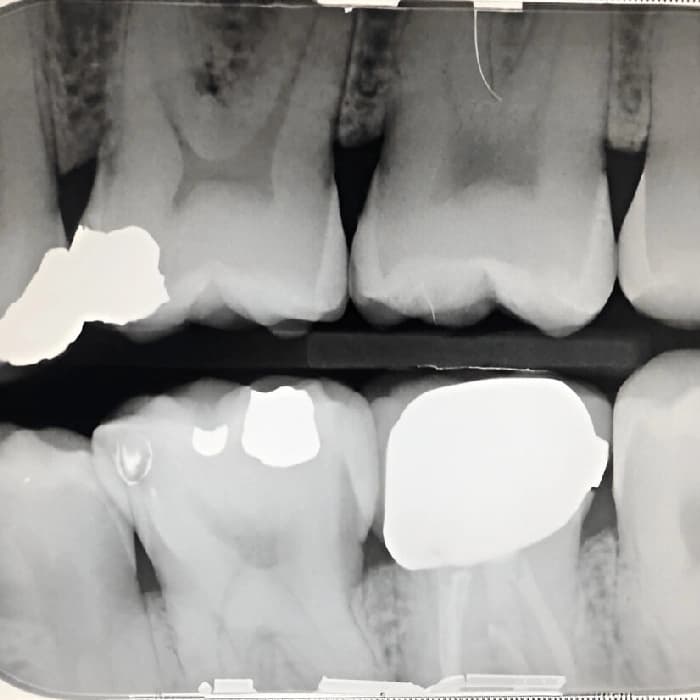

عکسهایی برای بررسی پوسیدگی بین دندونها و وضعیت استخوان در اطراف

عکس بایت وینگ یکی از انواع رادیوگرافی دندان است که بهویژه برای بررسی وضعیت دندانهای خلفی، بررسی پوسیدگی دندانها و ارزیابی مشکلات بین دندانی کاربرد دارد. این نوع عکس معمولاً برای بررسی پوسیدگیهای دندانی که در میان دندانها قرار دارند یا بهمنظور بررسی نواحی دندانهایی که در تماس با یکدیگر قرار دارند، استفاده میشود. در این عکس، دندانپزشک میتواند تغییرات دندانی یا مشکلات ساختاری دندانها و لثهها را مشاهده کرده و تشخیص دقیقتری بدهد.

بیمارانی که علائمی مانند پوسیدگی دندان، درد در ناحیه دندانها، خونریزی لثه، یا مشکلات جویدن غذا دارند، ممکن است به عکس بایت وینگ نیاز داشته باشند. این علائم میتوانند نشاندهنده مشکلاتی در دندانها یا لثهها باشند که با استفاده از این نوع رادیوگرافی قابل شناسایی است. علاوه بر این، این نوع عکس برای افرادی که نیاز به ارزیابی دقیقتری از وضعیت دندانهای خود دارند یا برای پیگیری درمانهای قبلی، بسیار مفید است.

عکس بایت وینگ یکی از روشهای مؤثر برای تشخیص مشکلات دندانی و لثهای است که به دندانپزشکان کمک میکند تا مشکلات بین دندانی، پوسیدگیها، و سایر مشکلات ساختاری دندانها را شناسایی کنند. این روش بدون درد است و بهطور سریع و دقیق اطلاعات لازم را برای برنامهریزی درمانی فراهم میآورد. هزینه عکس بایت وینگ به عوامل مختلفی بستگی دارد و برای دریافت هزینه دقیقتر، مراجعه به دندانپزشک متخصص توصیه میشود. این رادیوگرافی بهویژه برای افرادی که مشکلات دندانی جزئی دارند یا بهمنظور پیگیری وضعیت دندانها نیاز به ارزیابی دارند، مفید است.